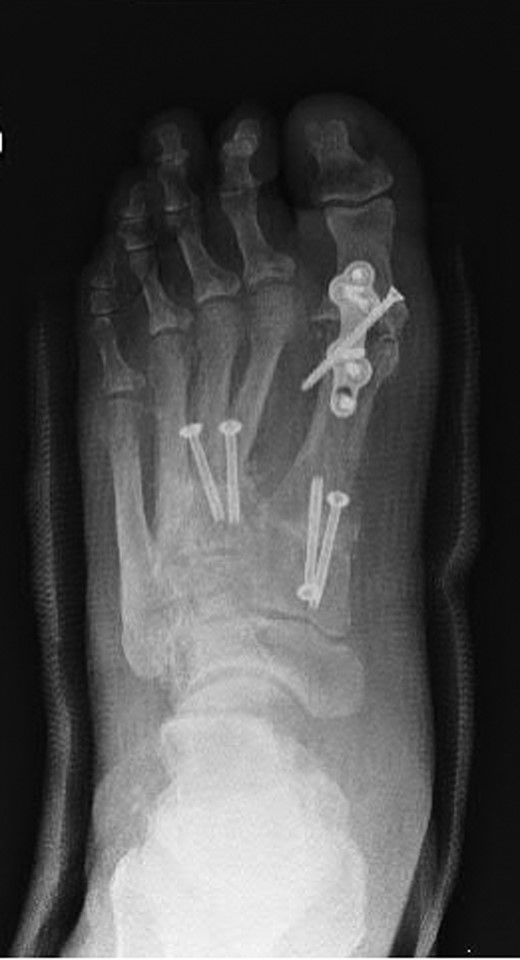

Oblique radiograph of the left foot following first MTPJ and first, second and third TMTJ fusions.

Dorsoplanter radiograph of the left foot following first MTPJ and first, second and third TMTJ fusions.

The patient had undergone previous diagnostic and therapeutic corticosteroid injections into his first, second and third TMTJs, temporarily improving the mid-foot pain. The patient wanted complete pain resolution and so underwent arthrodesis of these joints and the first MTPJ (Figs 6 and 7). Operative findings confirmed radiographic findings with the presence of an additional middle cuneiform covered with degenerate cartilage proximally and distally.

Another clinical significance could arise in the case of a second TMTJ arthrodesis. The dilemma is presented as to whether or not fusion be performed between the second metatarsal base and the additional ossicle (Figs 6 and 7), or to span the additional ossicle fusing the second metatarsal to the middle cuneiform. Either way, careful assessment of the anatomy must be performed preoperatively to ensure that all joint surfaces are prepared and arthrodesed appropriately.